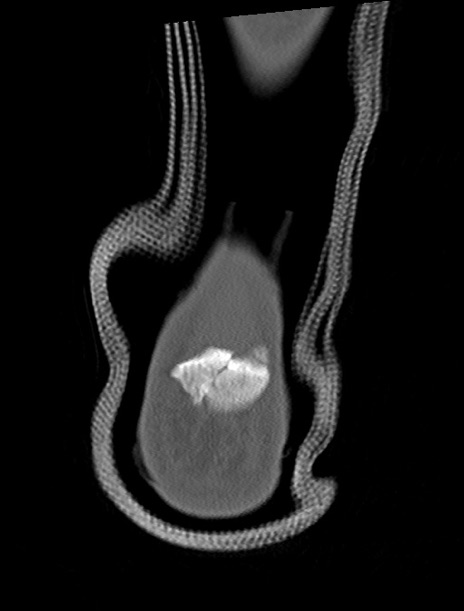

左足関節CT

3D再構成